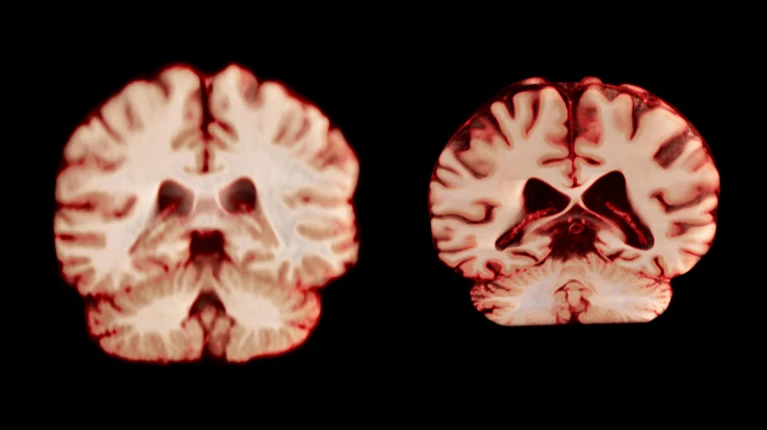

Во время своей работы ученые проанализировали данные 12,5 тыс. изображений МРТ, полученных от более чем 4,7 тыс. человек с интервалом сканирований в три года. Они сравнили изменение структур мозга участников по мере старения, включая объем серого вещества и гиппокампа.

Однако результаты исследования поставили ученых в тупик: как оказалось, мужской мозг стареет быстрее, чем женский: например, за год постцентральная извилина у мужчин сократилась примерно на 2%, а у женщин — лишь на 1,2%.